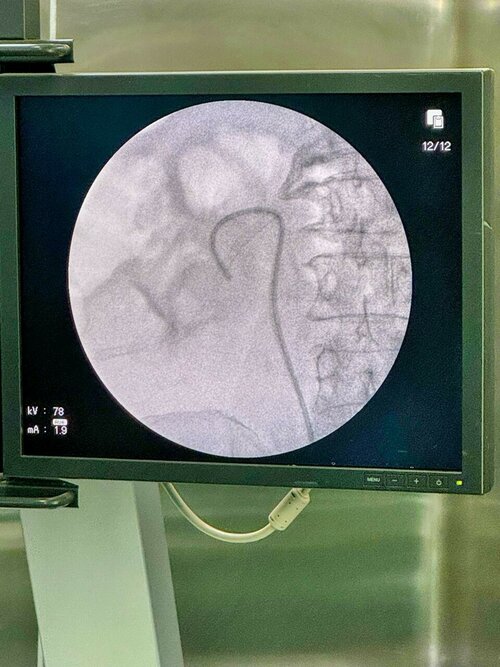

Expert Urethral Stricture Treatment by Dr. Bhoopat Bhati | Urologist in Viman Nagar

A bulbar urethral stricture is a narrowing of the urethra, the tube that carries urine out of the body, in the bulbar region (near the ...